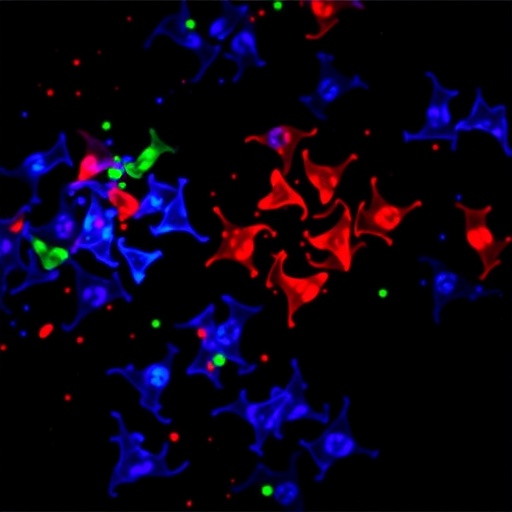

C/EBPγ Drives EMT and DNA Repair in Lung Cancer

In a landmark study that could fundamentally change our understanding of lung adenocarcinoma progression and treatment resistance, researchers have uncovered...